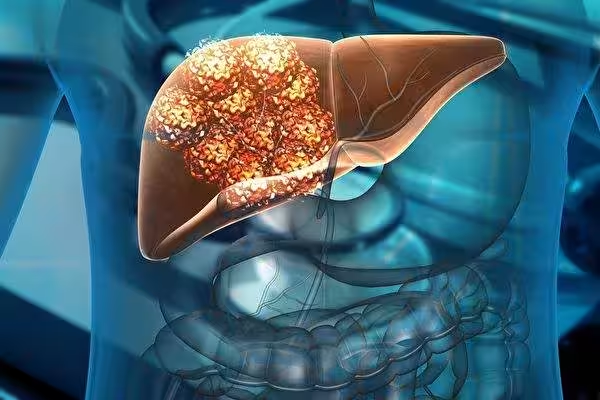

但是肝臟雖然是有再生力,但對肝硬化患者則不能再擁有這種「超能力」。

因為肝硬化會使大量的肝細胞壞死或病變,所以肝硬化往往是不可逆的。